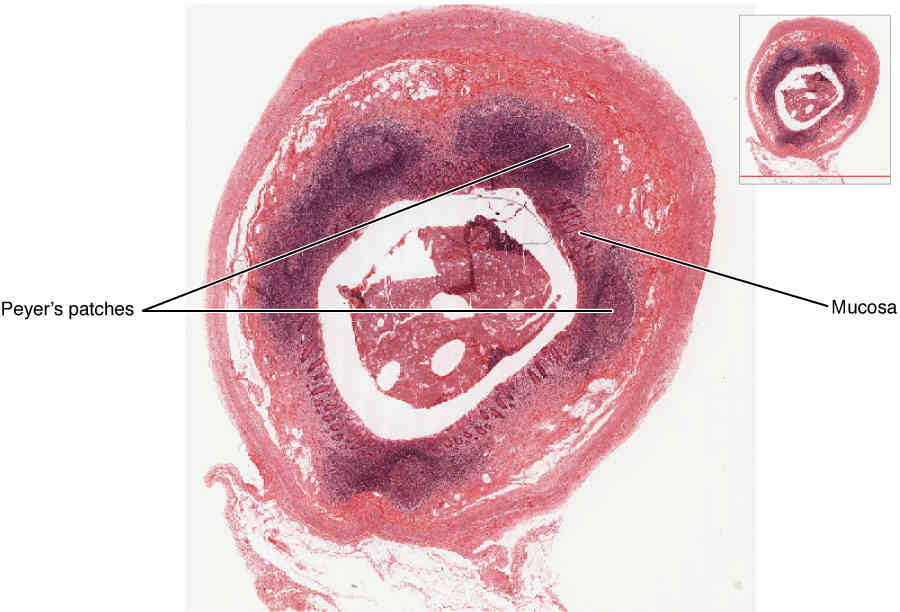

This page is under construction. For now, it is just a resource of the images found in the OpenStax Anatomy and Physiology Handbook. It wil slowly change into a revision tool. Each slide has a number. Use this to refer to the slide. When completed, it will have an unlabelled section, with labelled slides in parallel. On the unlabelled slides, write your answer and use the labelled slide to assess yourself. Keep track by also noting the number on each slide. Improvement at each attempt is important, more so than full marks on a first attempt.